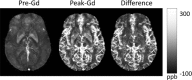

In MRI, the main magnetic field polarizes the electron cloud of a molecule, generating a chemical shift for observer protons within the molecule and a magnetic susceptibility inhomogeneity field for observer protons outside the molecule. The number of water protons surrounding a molecule for detecting its magnetic susceptibility is vastly greater than the number of protons within the molecule for detecting its chemical shift. However, the study of tissue magnetic susceptibility has been hindered by poor molecular specificities of hitherto used methods based on MRI signal phase and T2* contrast, which depend convolutedly on surrounding susceptibility sources. Deconvolution of the MRI signal phase can determine tissue susceptibility but is challenged by the lack of MRI signal in the background and by the zeroes in the dipole kernel. Recently, physically meaningful regularizations, including the Bayesian approach, have been developed to enable accurate quantitative susceptibility mapping (QSM) for studying iron distribution, metabolic oxygen consumption, blood degradation, calcification, demyelination, and other pathophysiological susceptibility changes, as well as contrast agent biodistribution in MRI. This paper attempts to summarize the basic physical concepts and essential algorithmic steps in QSM, to describe clinical and technical issues under active development, and to provide references, codes, and testing data for readers interested in QSM.